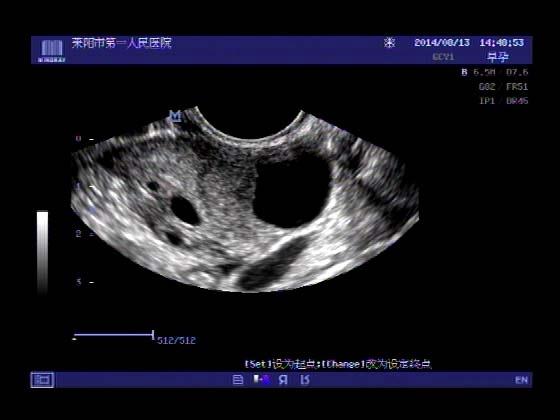

超声入门贴341:宫外孕(阴超的魅力)

女,32岁,停经15天,

一周前在上极医院检查:化验尿HCG阳性,血HCG400多,超声检查问见明显孕囊,让随访。

看见卵黄囊啦~孕囊型的吧?

还能看到卵黄囊,真不错